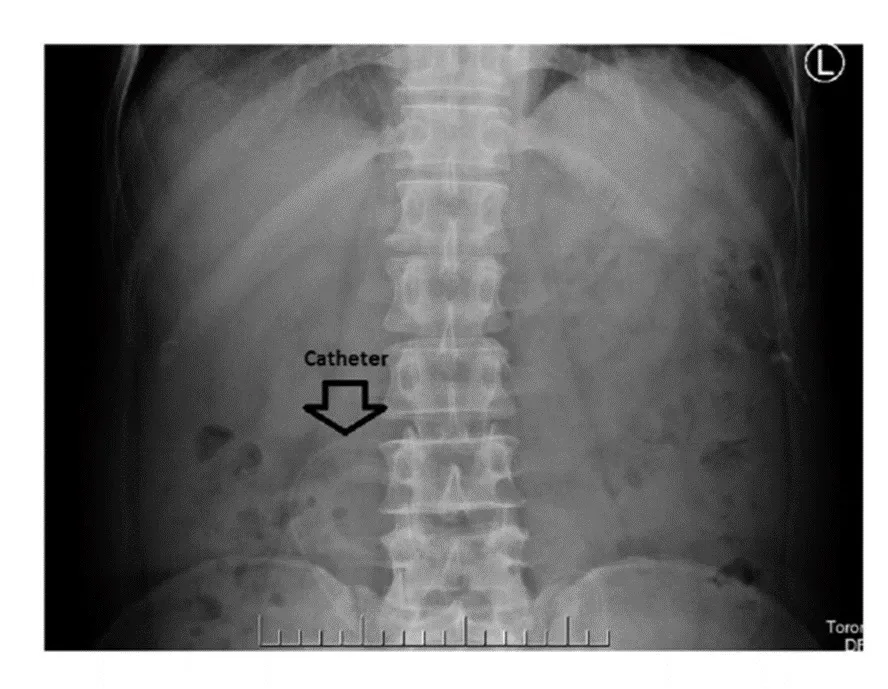

* Constipação com migração da ponta do cateter para fora da pelve; Deve-se tratar a constipação e, se falha, em retornar a ponta do cateter para a posição correta, considerar reposicionamento da ponta do cateter.

Migração da ponta do cateter.